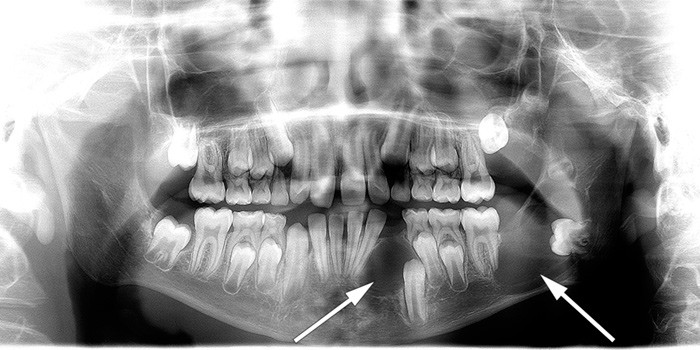

Pasientene må følges jevnlig med tanke på kjevecyster. Slike cyster kan bli store, og tennene kan bli forskjøvet (6, 8). Vi anbefaler at undersøkelse for kjevecyster gjøres med digitalt ortopantomogram (OPG) (fig 2) hos en kjeve-/ansiktsradiolog eller tannlege som er godt kjent med innstilling og tolking av denne undersøkelsen. Tannhelsekompetansesenteret (TAKO) ved Lovisenberg Diakonale Sykehus kan kontaktes ved spørsmål vedrørende tenner og kjeve.